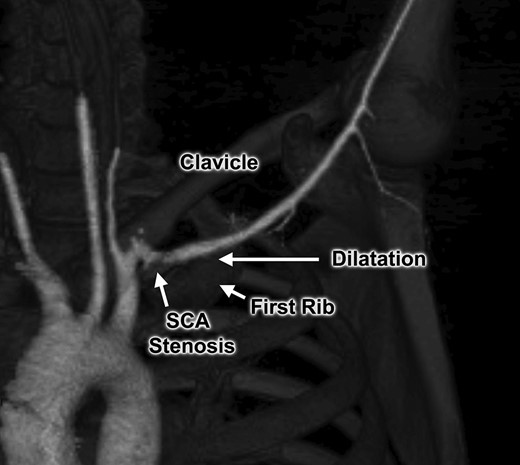

An otherwise healthy 44-year-old female nurse presented with a painful left arm and hand, 2 weeks after she had fallen onto the outstretched left arm while hiking. She sought medical attention when she developed Raynaud’s phenomenon and was unable to feel pulses at the wrist, and clinical evaluation suggested thrombosis of the left brachial, radial and ulnar arteries. Contrast-enhanced computed tomography (Figs 1 and 2) and catheter-based arteriography (Fig. 3) confirmed the diagnosis and showed that while there was no cervical rib or other bony abnormality, there was focal stenosis of the left subclavian artery at the level of the first rib with mild post-stenotic dilatation. These findings indicated that the subclavian artery was the source of thromboembolism and the patient was successfully treated with catheter-based thrombolysis to resolve the acute obstruction. She was discharged on a direct oral anticoagulant but returned within several weeks after recurrence of symptoms. She was found to have rethrombosis and again underwent thrombolysis, followed by anticoagulation with an alternative agent, and was then referred to our specialized TOS center for surgical treatment.

Computed tomography angiogram demonstrating focal area of left subclavian artery (SCA) compression between the first rib and clavicle.